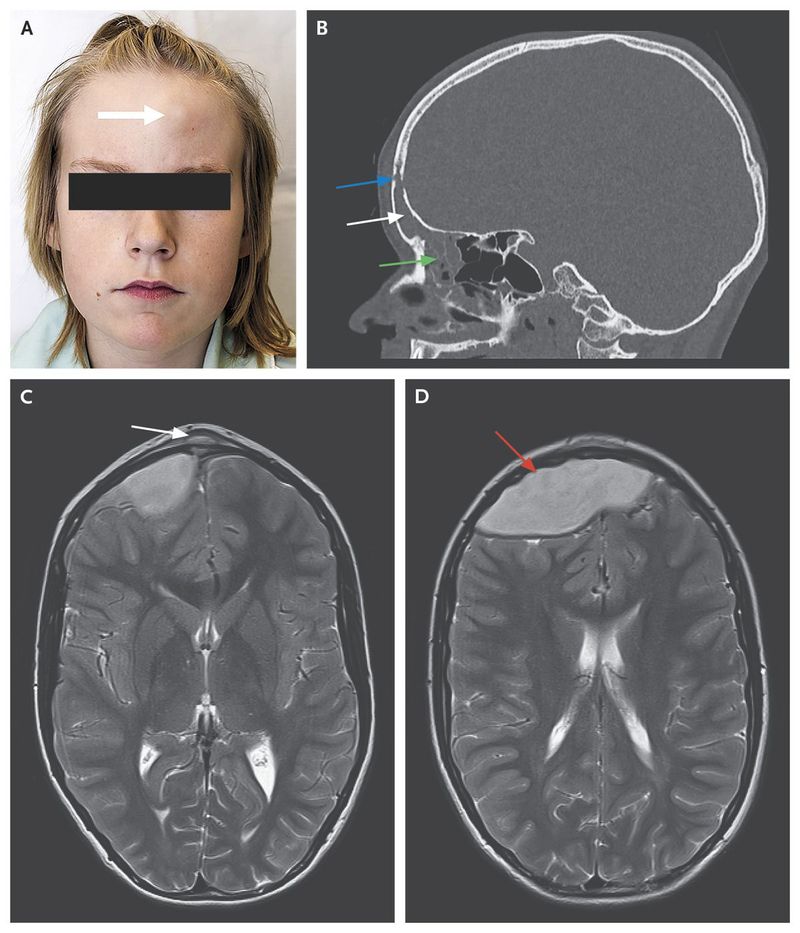

A previously healthy 13-year-old boy presented to the otorhinolaryngology clinic with soft, well-demarcated, painless swelling of the forehead (Panel A, arrow). He had no definite symptoms of sinusitis but had had a headache and fluctuating fever for 3 weeks. He had no neurologic deficit or abnormality on physical examination. A blood chemical profile showed a C-reactive protein level of 29 mg per liter and a white-cell count of 11,900 per cubic millimeter. Computed tomography revealed unilateral opacification of the left frontal and ethmoid sinuses (Panel B, white and green arrows, respectively) as well as defects in the frontal bone (Panel B, blue arrow). T2-weighted axial magnetic resonance images (MRIs) showed a subperiosteal abscess in the forehead (Panel C, arrow) and a 3 cm×5 cm×8 cm epidural abscess (Panel D, arrow). There was no involvement of the venous sinuses. A combined neurosurgical and otolaryngologic approach was used to surgically manage the frontal sinusitis and associated epidural abscess. Cultures grew Streptococcus intermedius. The patient was treated with intravenous antibiotic agents for 4 weeks after surgery. He remained well, with no neurologic sequelae or residual abscess observed clinically or on follow-up MRI obtained 1 month after drainage. Pott's puffy tumor is a rare clinical entity characterized by osteomyelitis of the frontal bone and associated subperiosteal abscess, usually related to frontal sinusitis; intracranial extension is a potential complication.